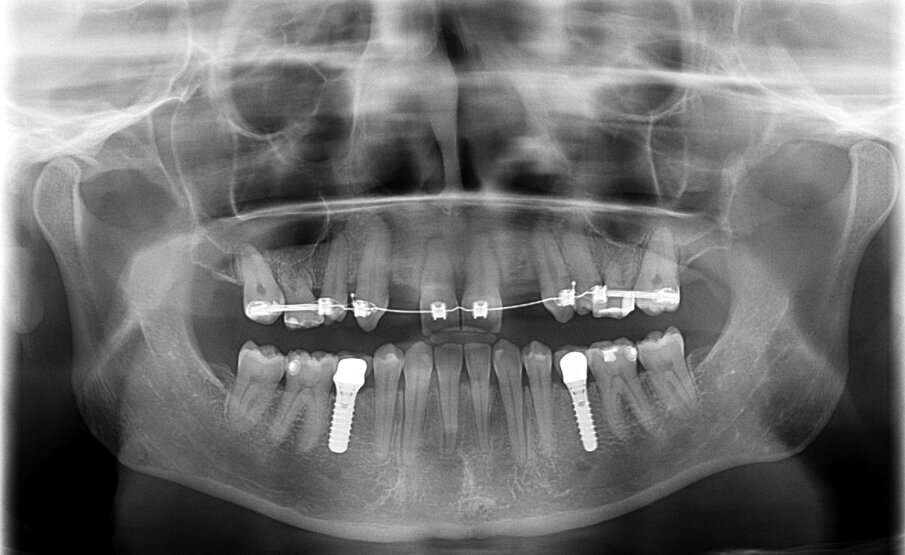

In samenspraak met de patiënte en in goed overleg met de behandelend orthodontist werd besloten de implantaten op de posities 13 en 23 te verwijderen, de cuspidaten naar distaal te verplaatsen en de angulatie van de elementen te corrigeren, zodat het plaatsen van twee implantaten op de posities van de laterale incisieven goed mogelijk zou worden (afbeelding 5 en 6).

Door de regulatie van de cuspidaten naar distaal is botappositie opgetreden, waardoor bij het plaatsen van de twee implantaten een minimale botopbouw volgens een GBR-techniek noodzakelijk was (afbeelding 7-9). Via digital smile design werd de uiteindelijke vorm gesimuleerd (afbeelding 10 en 11). Er werden twee verschroefde zirkonium kronen met opgebakken porselein vervaardigd voor de implantaten en er werden facings van lithiumdisilicaat gemaakt bij de centrale incisieven en cuspidaten (afbeelding 12-17).